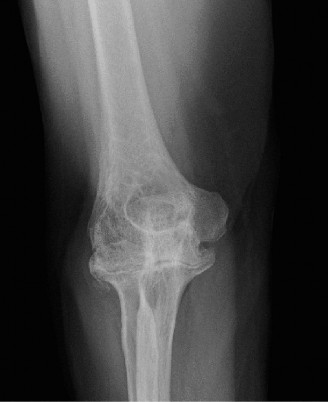

The correct answer is (E). Given that her rotator cuff has atrophied and has fatty infiltration to the point where there are equal parts fat and muscle, this is considered an irreparable rotator cuff tear. Repair should not be attempted because of poor outcomes following repair (see last two paragraphs of this discussion below). A reverse total shoulder arthroplasty is an alternative to repair that should be used in cases of massive, irreparable rotator cuff tears. It is a semi-constrained prosthesis that restores function in patients with massive rotator cuff tears by constraining a concave humeral cap inferior to a semispherical glenoid component (glenosphere). This creates an inferior force-couple and a fulcrum that replaces the stabilizing function of the infraspinatus maintaining a center of rotation around which the shoulder can move. This allows the deltoid to abduct and flex the shoulder without causing the humerus to migrate superiorly and about the acromion. In an elderly patient with a massive, irreparable rotator cuff tear (as in this patient), a reverse total shoulder arthroplasty is the procedure of choice.

It should be noted that reverse total shoulder arthroplasty is also the procedure of choice in patients with cuff-tear arthropathy (aka rotator cuff arthropathy). Characteristics of cuff-tear arthropathy include superior migration of the humerus due to a massive rotator cuff tear, glenohumeral joint destruction, subchondral osteoporosis, and humeral head collapse (see Fig. 2–17). A reverse total shoulder

Figure 2–17_X-rays of a patient showing evidence of cuff tear arthropathy. The humerus is migrated superiorly, the glenohumeral joint is destroyed, there is subchondral osteoporosis, and the humeral head is collapsed. (From Ecklund KJ, Lee TQ, Tibone J, Gupta R. Rotator cuff tear arthropathy. _J Am Acad Orthop Surg. 2007;15(6):340–349.)